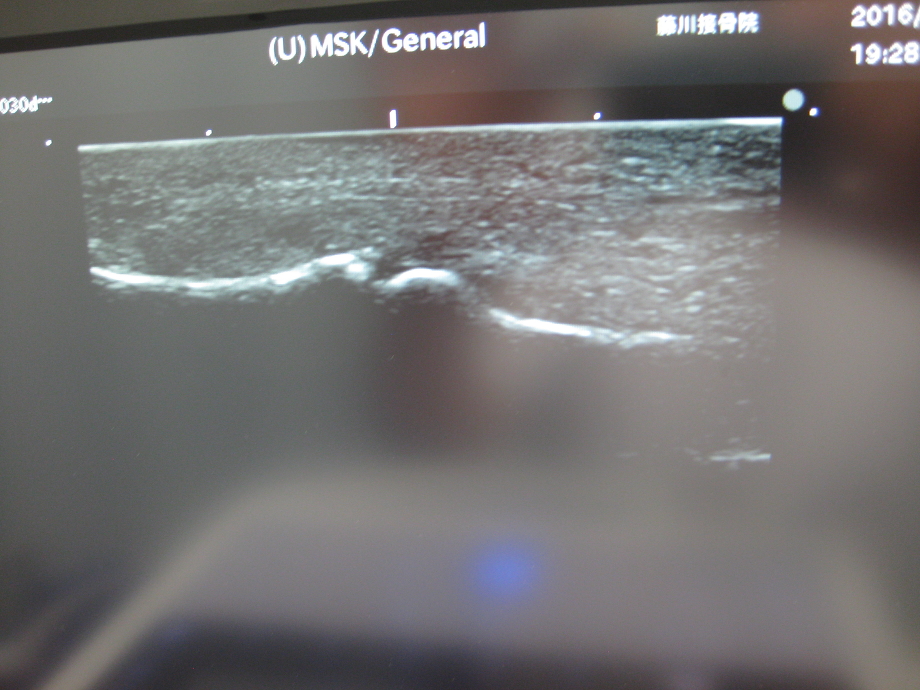

エコ-検査です

エコ-検査で掌側板による裂離骨折がみられます